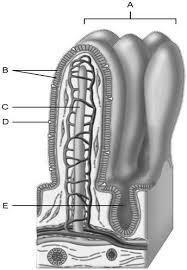

Mucosa

A

Duodenal glands found here

B

Smooth muscle layer.

C

Serosa.

D

Area of the lamina propria

A

Continuation of the mesentery

D

Absorptive cells that line the intestinal tract

B

Cell type specialized to secrete mucus into the lumen of the intestinal tract.

D

Wide lymph capillary located in the villus.

C

Paneth cells are found here.

E